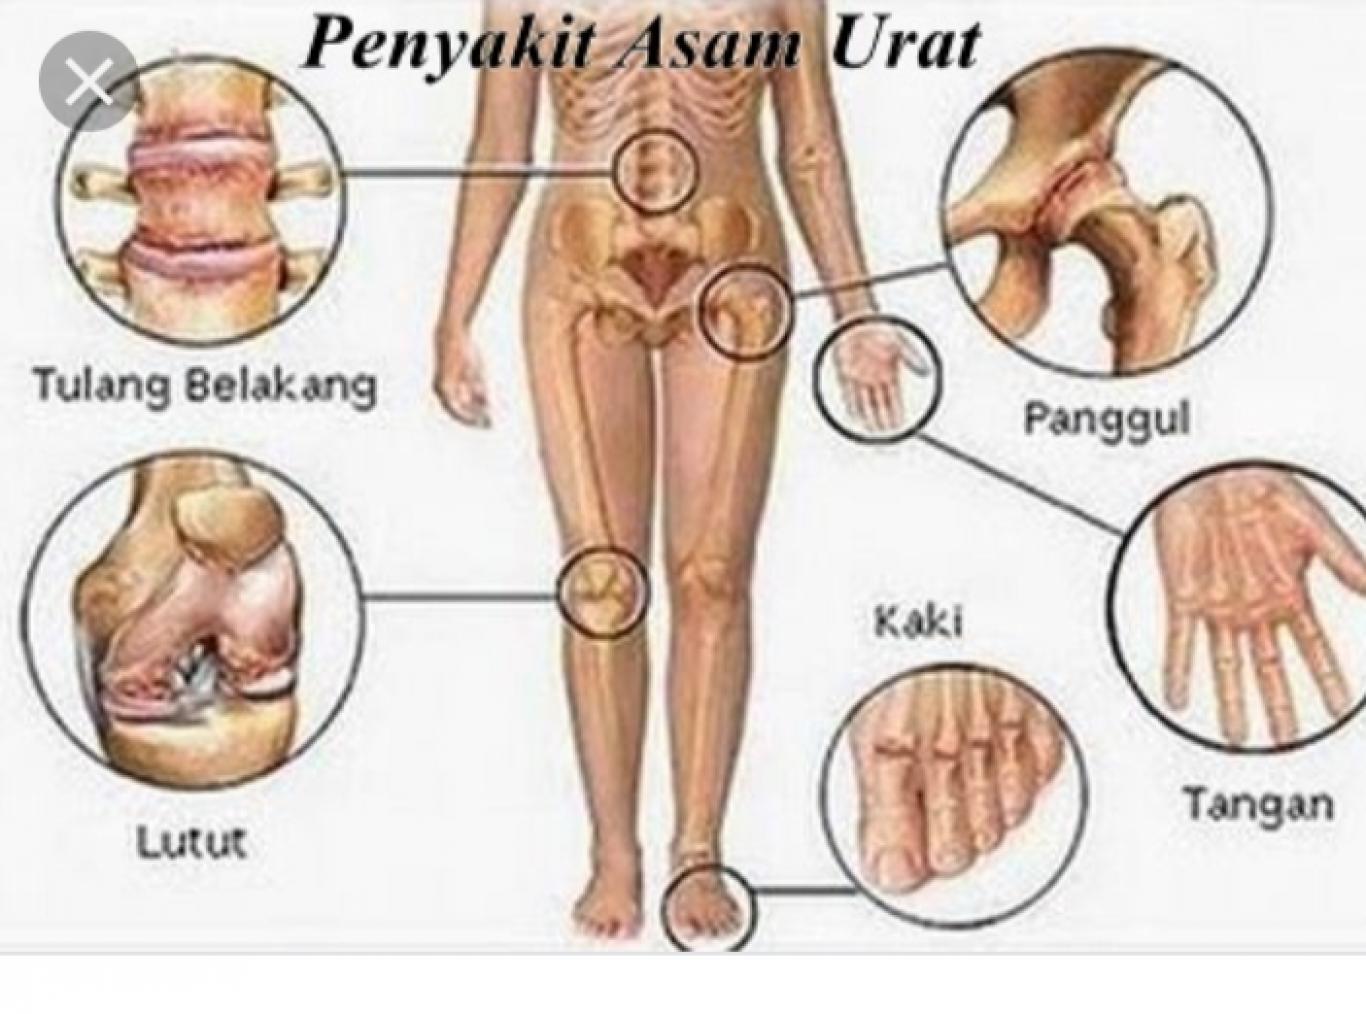

Penyakit Asam Urat Tanda Dan Gejala Penyebab Cara Mengobati Cara Mencegah

Penyakit Asam Urat Tanda Dan Gejala Penyebab Cara Mengobati Cara Mencegah

Pengertian Penyakit Asam Urat

Pengertian Penyakit Asam Urat

Pengertian Penyakit Asam Urat

Pengertian Penyakit Asam Urat